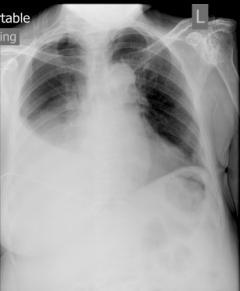

何女士與一般的在職媽媽無異,每天早上看著女兒出門上學後便上班,下班後買菜回家做飯,奉行少油少鹽無味精,好讓自己和家人都有較健康的飲食。約一年前,她突然發現自己咳嗽多了,更帶點血絲,氣喘得很,便向公司請了半天假去求診。醫生檢查過後,為何女士照了張肺片,竟發現右邊肺有肺積水的情況。醫生告之可能是因為肺癌引致的惡性肺積水,需要進一步檢查以極認。何女士聽後滿心疑惑,心想自己從不吸煙,飲食尚算健康,不可能患上肺癌,便斷然拒絕進一步的檢查。

雖然吸煙依然是肺癌的主要成因,但是非吸煙人士患上肺癌也並非罕見。香港胸肺學會名譽秘書古惠珊醫生指出,這類患者多數較年輕;在亞洲女性肺癌患者當中,非吸煙人士更佔了六至八成。在這類非吸煙患者中,致癌原因比較難以查找,吸入二手煙、石綿和沙塵、煎炸含高脂肪肉類時產生的油煙等,相信亦是肺癌的成因之一。「由於缺乏明顯的危險因素,肺癌初期病徵又不明顯,很多患者都會很遲才求醫,並已出現併發症。就像何女士的個案一樣,直到一整邊肺都積了水造成嚴重咳嗽,才找醫生診治。」 除了氣促和咳血外,肺癌的病徵還包括了胸口不適或疼痛,有部份病人會出現消瘦的狀況,但這些病徵都很容易被病人忽略。其他較明顯或嚴重的病徵還包括了發燒、因神經線受腫瘤壓迫而出現手痺或眼簾下垂、大靜脈受壓引致頸面腫脹,以及因骨轉移或伴癌綜合症而出現骨裂等症狀。「像何女士般已出現肺積水般,多代表腫瘤已刺激周邊組織引致發炎和血管擴張,病情多屬晚期。」古醫生說。

Caption :肺部右下側呈一片白濛濛,是典型肺積水的情況。